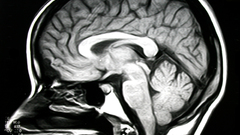

A brain is an organ that serves as the center of the nervous system in all vertebrate and most invertebrate animals. It is located in the head, usually close to the sensory organs for senses such as vision. It is the most complex organ in a vertebrate's body. In a human, the cerebral cortex contains approximately 14–16 billion neurons, and the estimated number of neurons in the cerebellum is 55–70 billion. Each neuron is connected by synapses to several thousand other neurons. These neurons typically communicate with one another by means of long fibers called axons, which carry trains of signal pulses called action potentials to distant parts of the brain or body targeting specific recipient cells.